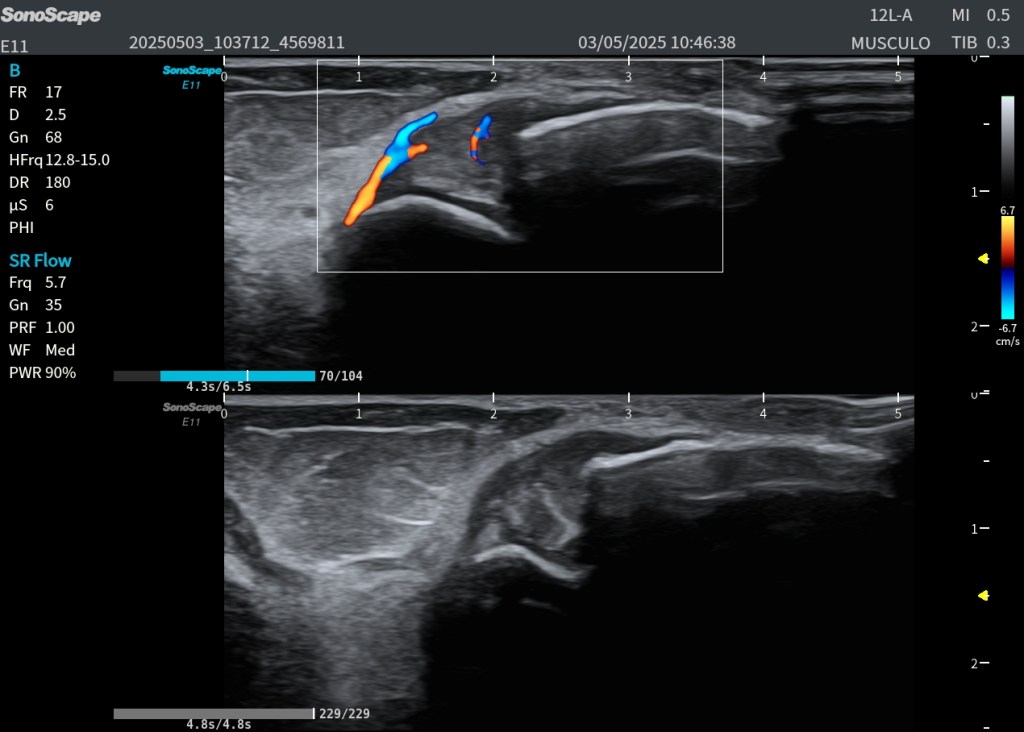

📹 Doppler: Vascularización del Ligamento

En el vídeo, mediante Doppler color, se evidencia aumento de la vascularización intraligamentaria. Este hallazgo no es característico de la fase aguda, sino más frecuente en lesiones subagudas o crónicas, donde existe neoangiogénesis asociada a la reparación tisular.